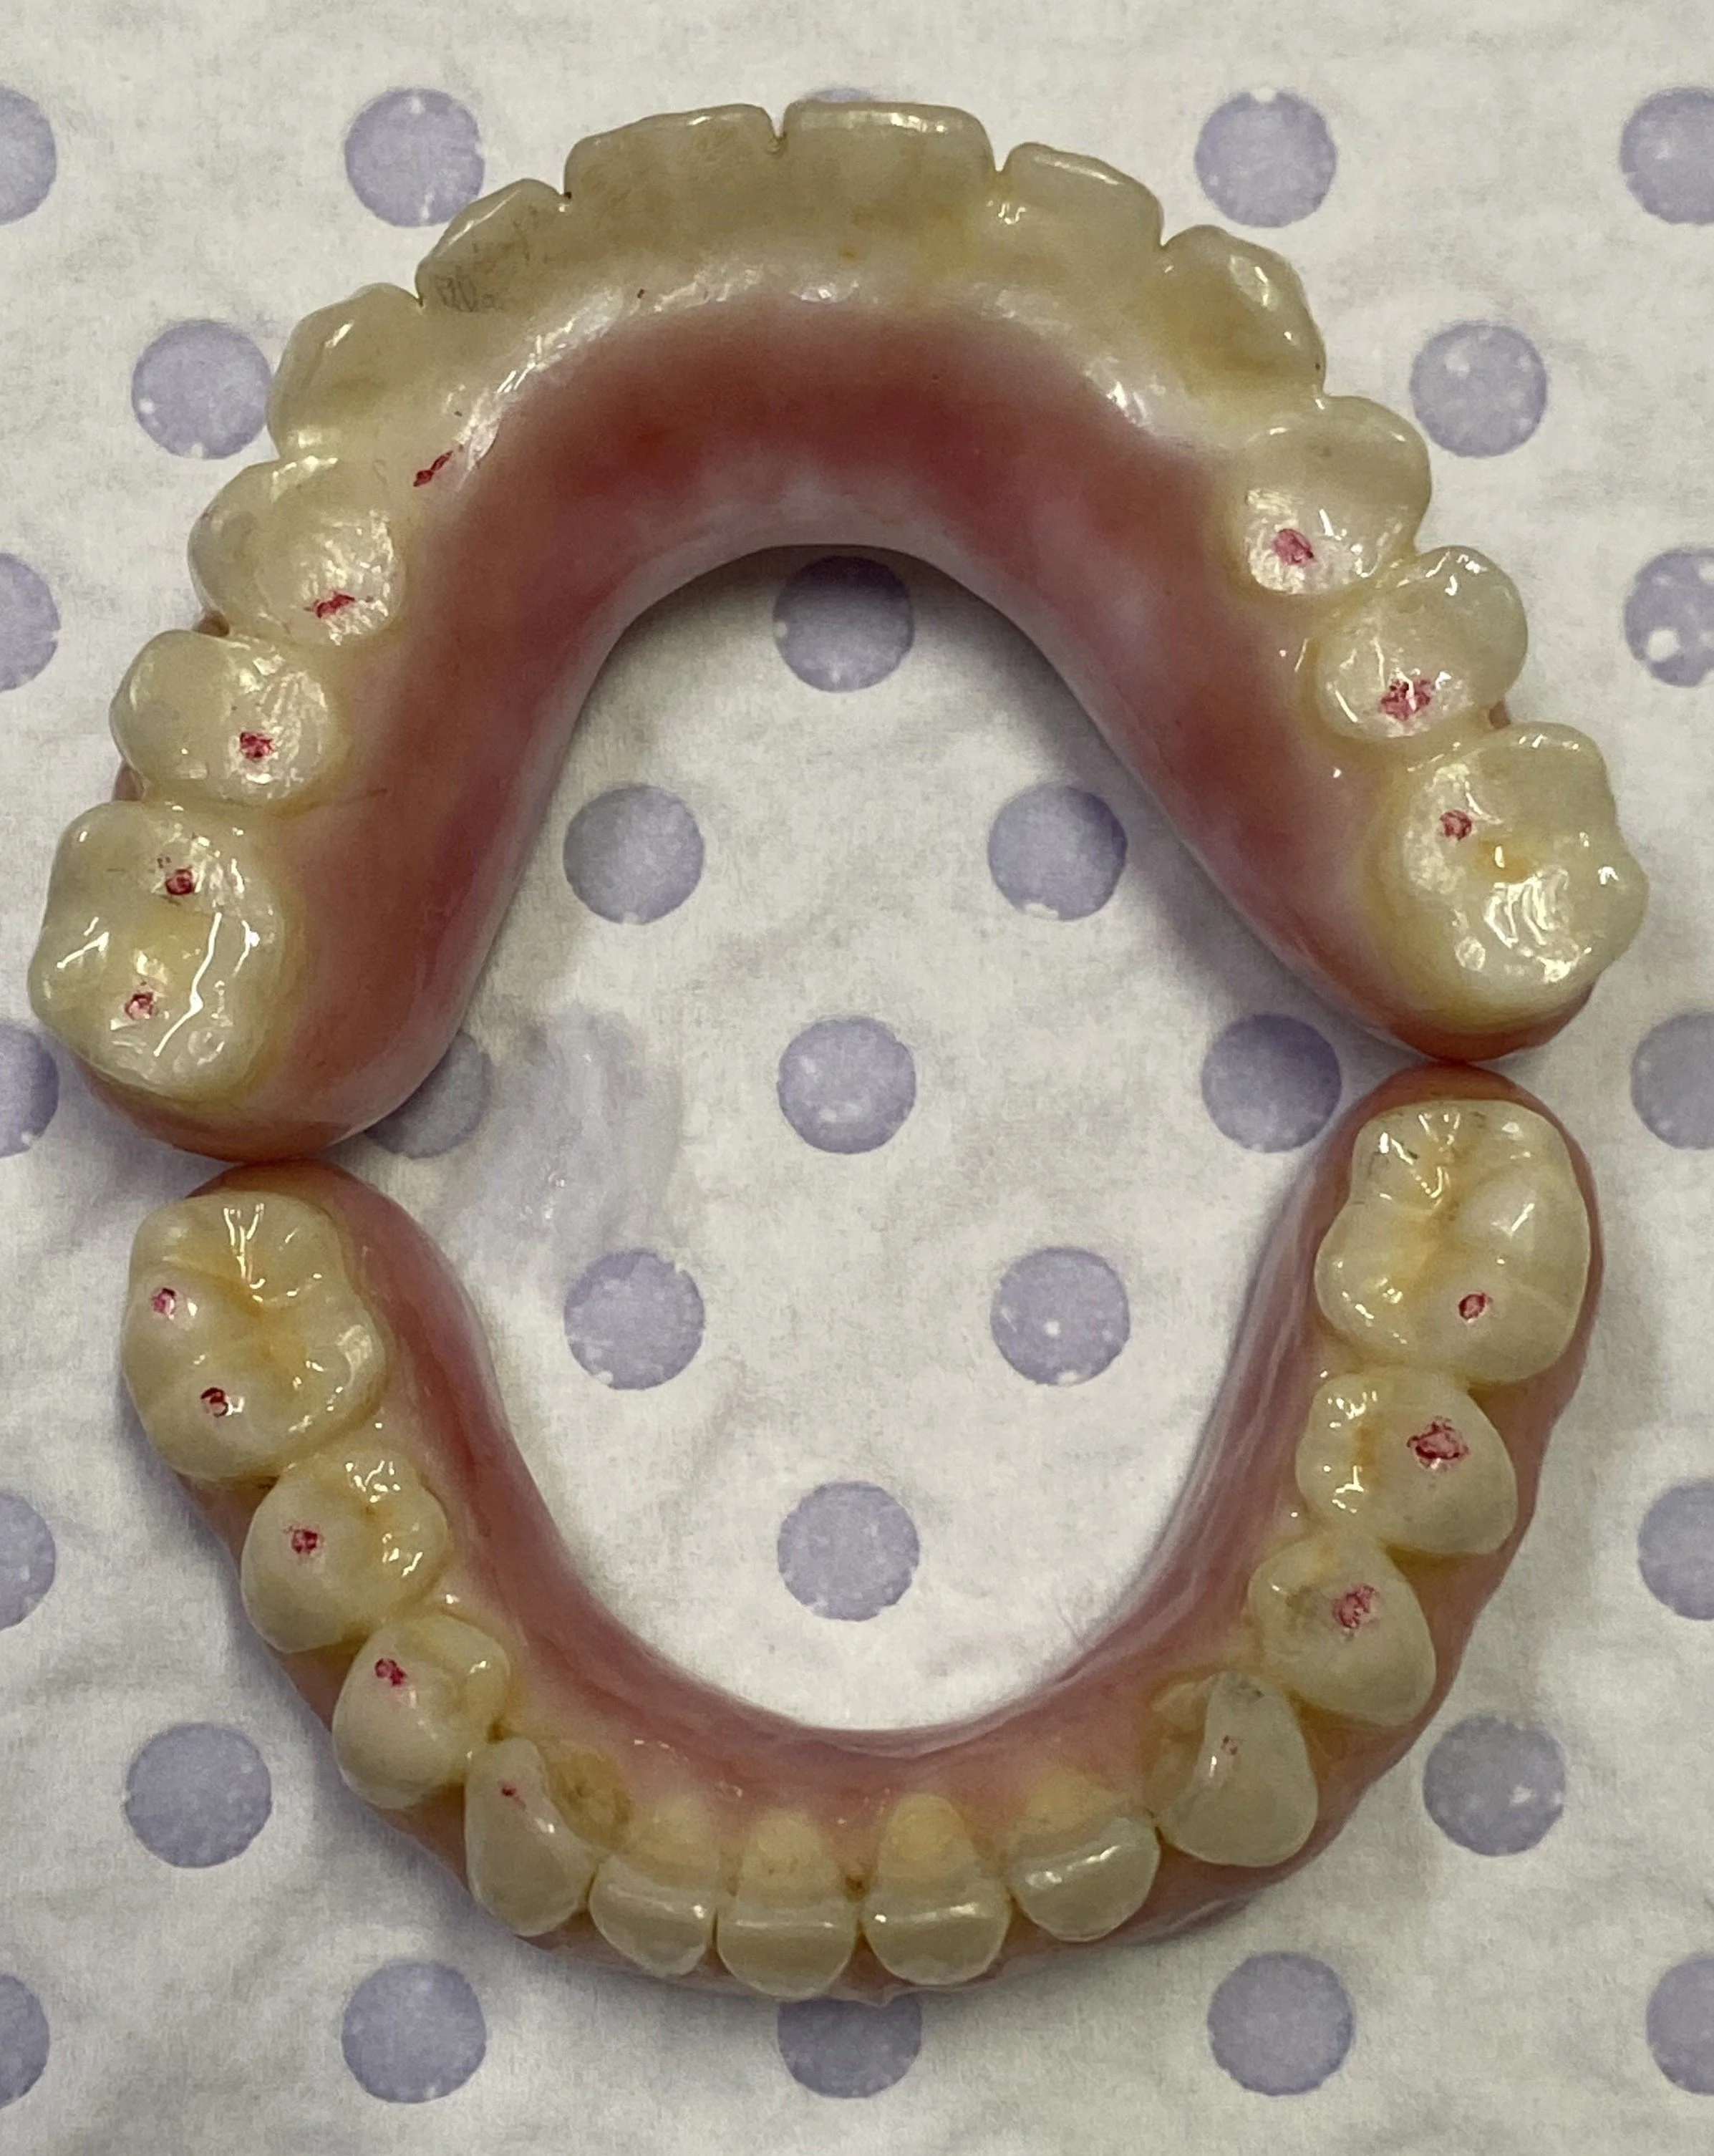

The underlying surface of the implant dentures with 4 nylon frictional sleeves in each denture.

This illustrates the lower zirconia implant denture with nylon friction sleeves along side a plaster model with titanium parallel abutments for a telescopic fitting Fixed-Removeable implant denture

This illustrates the upper zirconia implant denture with nylon friction sleeves alongside a plaster model with titanium parallel abutments for a telescopic fitting Fixed-Removeable implant denture.